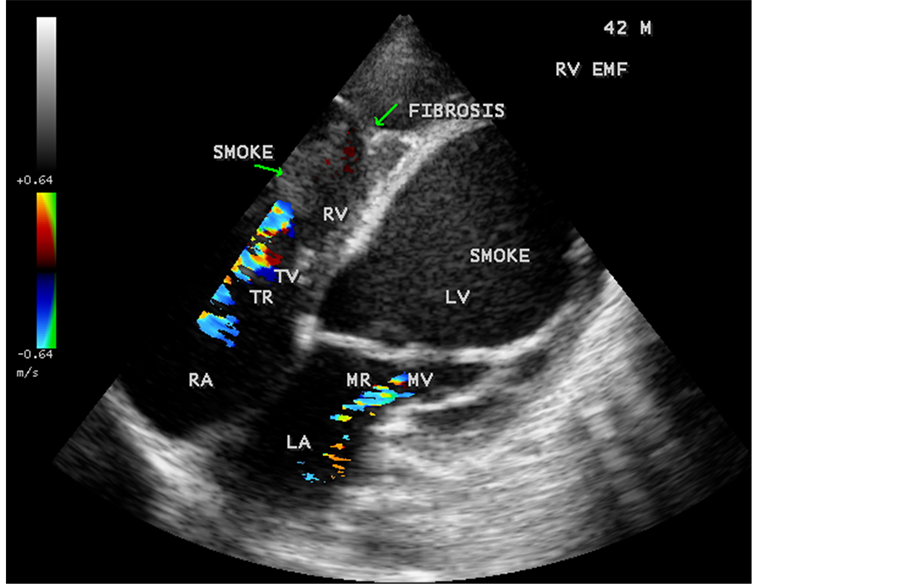

Figure 79. Tilted apical view showing the AV valve regurgitation with smoke (spontaneous echo contrast) in both ventricles in EMF in a 42-year-old male.

Figure 81. Tilted apical view showing the fibrous ridges of EMF in a 42-year-old male.

Figure 82. Tilted apical view showing the RV apical fibrosis and smoke (spontaneous echo contrast) in the left ventricle in a 42-year-old male.

RV EMF was detected antenatally in a 22-year-old woman with 8 months amenorrhea as in Figure 67. Endomyocardial fibrosis with left ventricular endocardial calcification and subvalvular fibrosis was detected in a new born with complete AV (atrioventricular) septal defect as shown in Figure 68 to Figure 72. EMF associated with fibrosis of papillary muscle and aneurysmal left ventricle is shown in Figure 74 and Figure 75 in a 56-year-old female. RV EMF associated with right sided pleural effusion, massive ascites and smoke (spontaneous echo contrast) in both ventricles are shown in Figure 76 to Figure 82 in a 42-year-old male. Classical case of RV EMF was shown in Figure 83 and Figure 84 in a 55-year-old male.